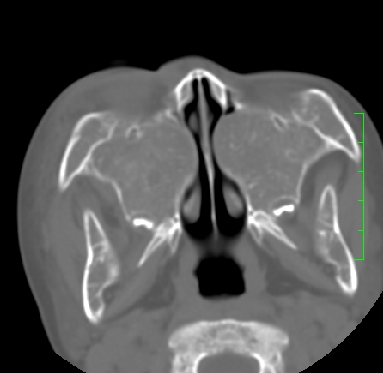

标题: PED1889:上颌窦病变

m,10y,外伤做ct